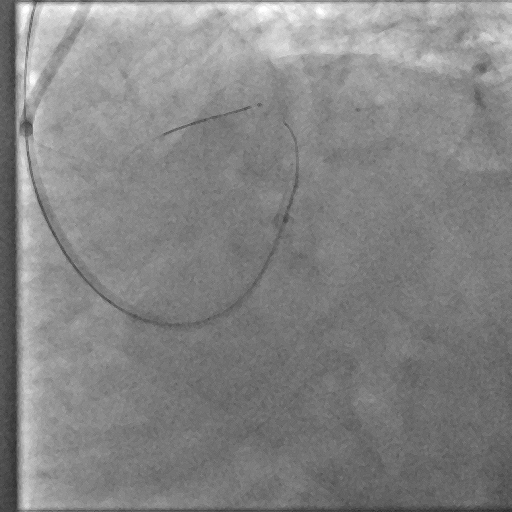

Coronary angiography demonstrated a right-dominant system with significant ostial LCx stenosis and a blunt ostial LAD chronic total occlusion, with a J-CTO score of 4. The RCA showed mild coronary disease and supplied collateral flow to the LAD territory, graded as Werner CC2.

Through bilateral femoral access, 7Fr EBU 3.5 and JR 4.0 catheters were engaged to the left main and RCA. With no antegrade entry, a retrograde marker wire and IVUS-guided antegrade puncture using Gaia Next 2 and Conquest Pro with Finecross failed, as both wires were deflected by the calcified cap despite tip modification with a secondary curve. A retrograde attempt using Gaia Next 2 and 3 with Finecross also failed.Suspecting LAD angulation, an antegrade re-attempt was performed using IVUS-guided puncture with a Conquest Pro 8-20 supported by a Supercross90 under retrograde wire guidance, successfully puncturing the proximal cap. Supercross was exchanged for Finecross, and the wire crossed distally, but Finecross and Corsair Pro XS could not advance due to the tight lesion. After proximal preparation and the anchor balloon technique in the LCx, the microcatheter advanced distally and the wire was exchanged for a workhorse wire. Retrograde injections confirmed true lumen position, and the LAD was predilated. IVUS showed mixed plaque and myocardial bridging in the mid LAD and mixed plaque at the ostial LCx. Further preparation was performed with a 3.5 mm scoring balloon. A hybrid strategy using a 4.0¡¿20 mm DCB for the LCx and a 4.0¡¿32 mm DES from LM to LAD, followed by 5.0 and 4.0 NC balloons for post-dilatation, achieved final TIMI 3 flow without complications.